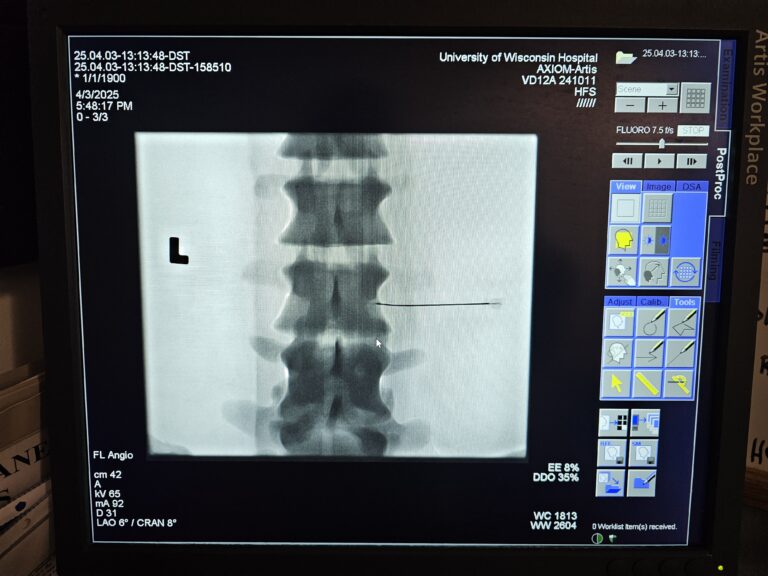

This station, led by Monica Cooley, MD and Nicholas Laucis, MD, combined diagnostic imaging with interventional pain procedures like epidural steroid injections.

Dr. Cooley and Dr. Laucis showed students how to perform the interventional procedure using the images scanned by the C-arm as a guide for administering epidural steroid injections on a mannequin. An anatomical model of the spine was also used as a visual aid when describing and demonstrating the interventional procedure. Students administered the injection and received guidance and encouragement from their instructors and peers.